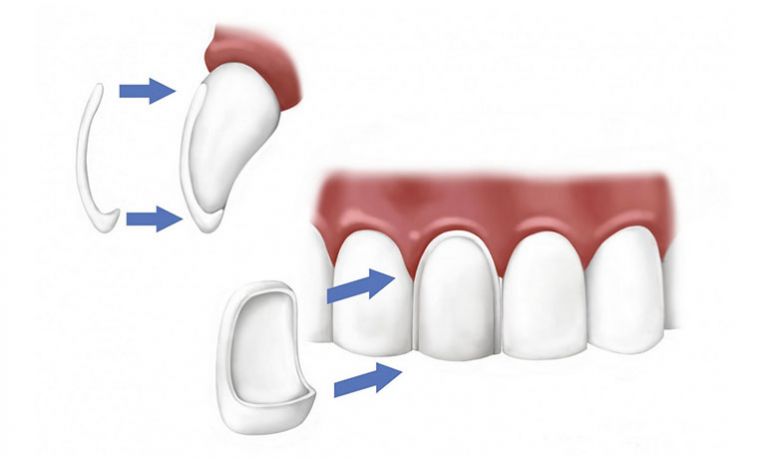

Soluzione per la perdita di un singolo dente

Continua